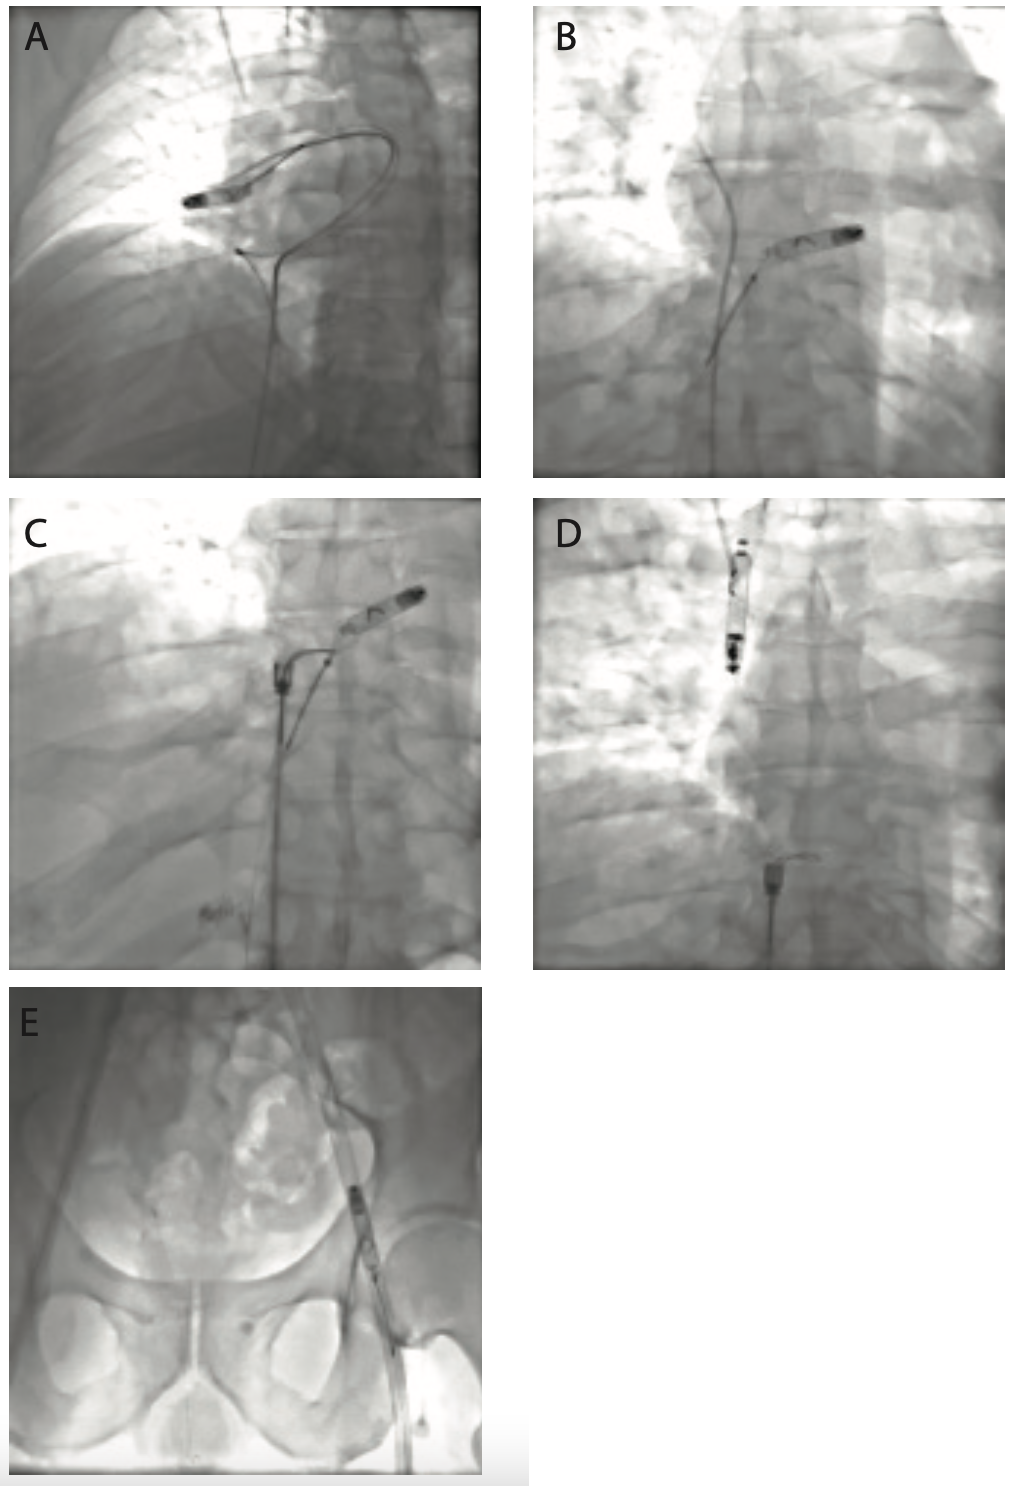

(A) The leadless pacer with docking button proximal to the EN Snare device. Also shown is the 6 French (F) diagnostic catheter used for angiography. (B) The lead- less pacer captured and retracted into main pulmonary artery by the EN Snare device. (C) The failed attempt to switch the leadless pacer from the EN Snare to the NRC catheter. Consequently, the pacer floated into the superior vena cava (SVC) with the docking button positioned distally. (D) The pacer was recaptured by the EN Snare device from the SVC, brought into the right atrium, and captured by the NRC at the other end to attempt the switch. (E) We were unable to maneuver the screw-in end into the safety sheath of the NRC. (F) The NRC approach was abandoned, and the pacer was recaptured and removed from the NRC system with the snare from the docking end. (G) The pacer was wrestled free from the right atrium and removed through the inferior vena cava (IVC). (H) The pacer suc- cessfully lodged within the 18F sheath in the common femoral vein.

The patient was brought into the hybrid operating room and intubated after general anesthesia was administered. A pre-extraction pulmonary angiography was performed through a multipurpose catheter, ruling out any perforation or bleed (Figure 2 shows actual images of the pacer retrieval procedure and Figure 3 features a schematic of the sequence). An 18-30 mm EN Snare catheter (Merit Medical) was then advanced to capture the docking button on the leadless pacemaker. When the pacer was in the main pulmonary artery, another angiogram confirmed no perforation or vessel rupture, but did reveal an embolized branch of the distal vessel. The Nanostim Retrieval Catheter (NRC) (Abbott) was steered into the right atrium while the EN Snare, along with captured device, was retracted into the right atrium. Following the Nanostim device instructions for use (IFU), we next needed to switch the device from the EN Snare catheter to the NRC before retracting the device via the inferior vena cava (IVC). We released the device from the EN Snare, but before we could capture the device with the NRC, the pacemaker moved into the superior vena cava (SVC). The docking button was positioned toward the cranial aspect of the SVC, complicating plans to use the NRC. The EN Snare was used again and advanced up the SVC. We were able to successfully capture the leadless pacemaker by advancing the EN Snare loop over the body of the device and returned the device to the right atrium. On the second attempt, the pacer was released from the EN Snare and captured by the NRC. The NRC snare loop became fixed around the body of the device, and despite multiple attempts, we were unable to move the loop to the docking button or align the device in a coaxial fashion to the NRC. Plans to use the NRC were abandoned and the pacer pulled out of the NRC loop snare as the EN Snare loop was able to capture the docking button. The EN Snare catheter, along with the captured device, were withdrawn in an 18 French (F) sheath and retracted all the way to the hub. Since we had not used a Perclose system (Abbott Vascular) and the patient was heparinized, we decided to reintroduce a new sheath. The sheath with the embedded device was retracted 4 inches, nicked to introduce a 150 cm, .035-inch J wire, and a new 18F sheath was exchanged for later manual removal. The device was extracted from the sheath and sent to the company for analysis.